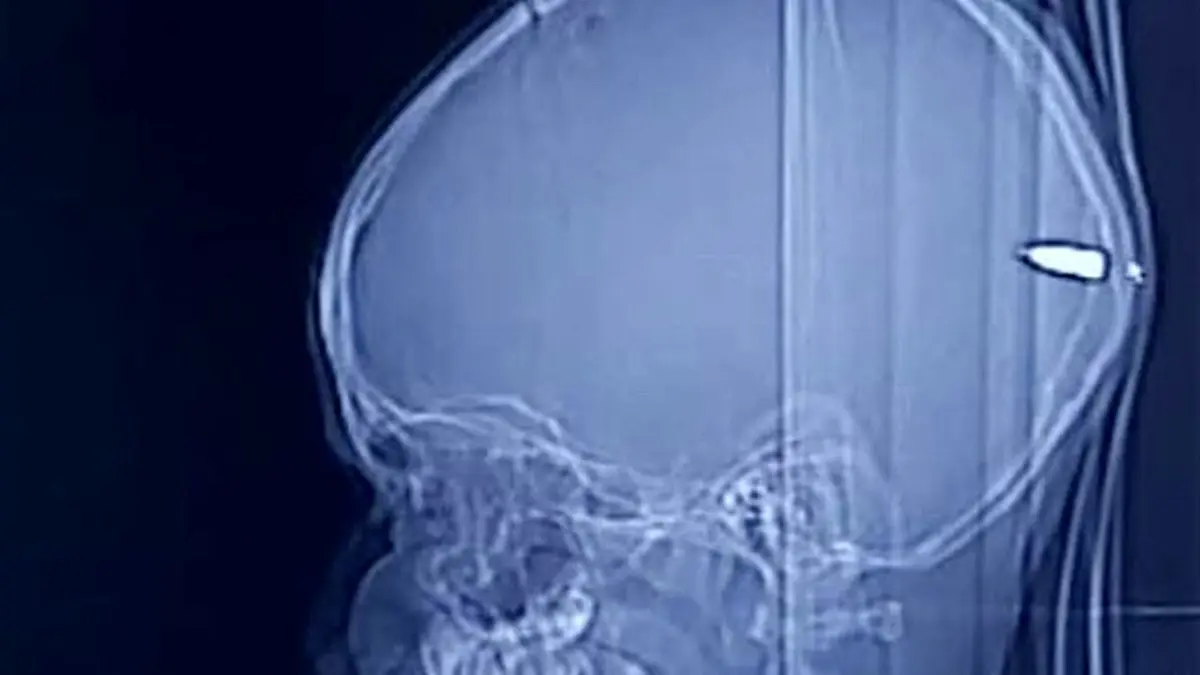

کشف یک گلوله در جمجمه کودک فلسطینی / او خوابالو شده بود + عکس

حوادث رکنا:پسر ۹ ساله فلسطینی که یک گلوله به پشت جمجمه اش اصابت کرده بود به جای مردن دچار خواب آلودگی شدید شد.

پس از انتقال پزشکان متوجه زخمی روی سر پسر شده و پس از انجام سی تی اسکن به وجود گلوله پی برده اند.

گای الور جراح مغز و اعصاب در این باره گفت: والدین پسر خبر نداشتند که به فرزندشان گلوله ای شلیک شده است.اما ما بلافاصله پسر را به اتاق عمل برده و تحت جراحی قرار دادیم و خوشبختانه از این حادثه جان سالم بدر برده است.